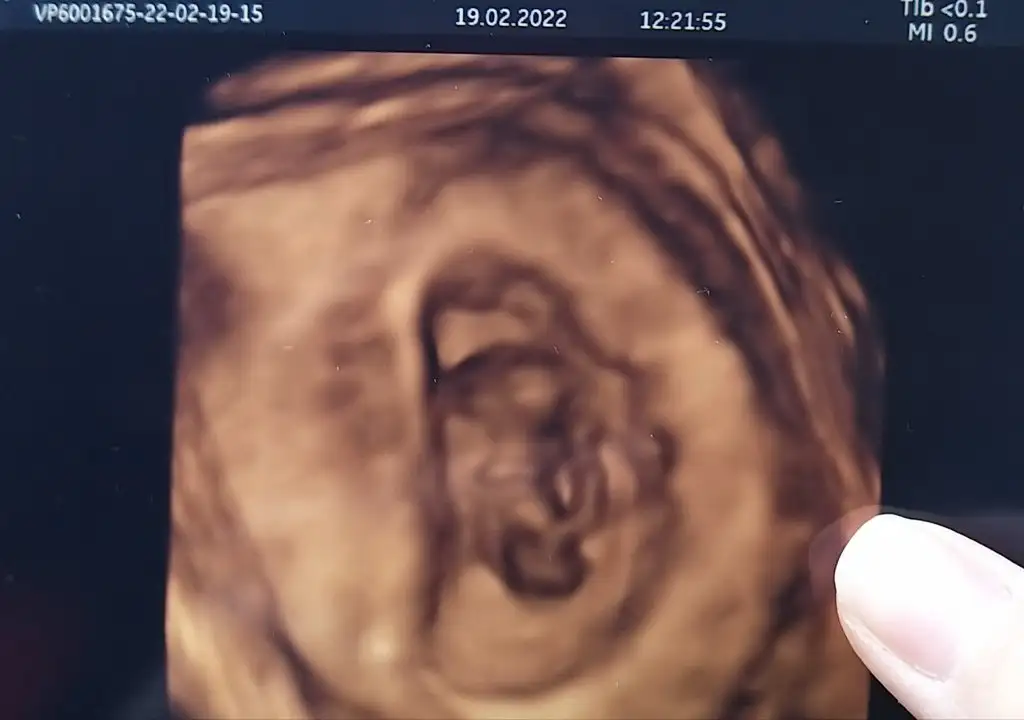

5 ve 14. haftaya kadar olan ultrasyon fotolarınızı paylaşın. Vajinadan mı yoksa karından mı çekildiğini ve kaç haftalık olduğunu da mutlaka belirtin.

canım kaç haftalık?Ay bende bende lütfen(karından ultrason görüntüleri)

15 şuan, görüntüler 13 haftalıktan göstermedi bebiş o gün :)canım kaç haftalık?